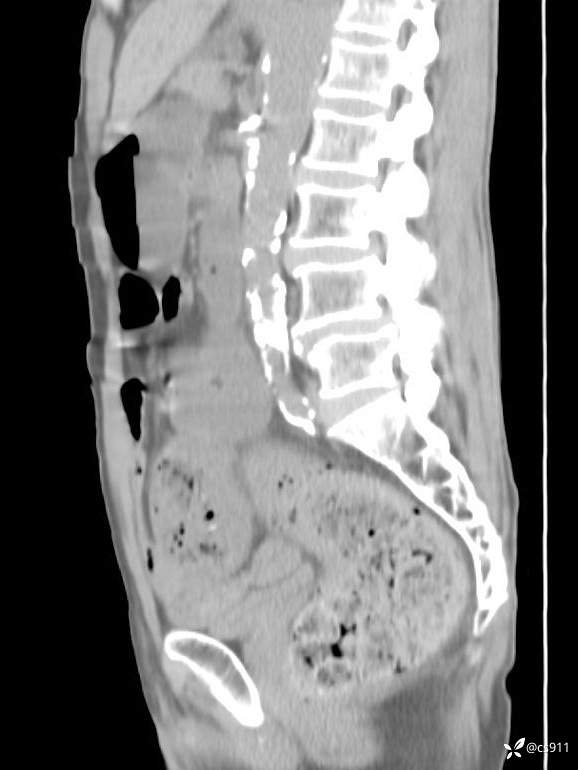

急腹症之急诊CT,原因?答案公布

男,77岁,腹痛、腹胀伴恶心呕吐1天。呕吐胃内容物,非喷射性呕吐,有咖啡色样胃内容物,诉有胃穿孔病史。查体:全腹平,下腹部压痛,全腹无反跳痛,叩诊呈浊音,移动性浊音阴性,肠鸣音减弱,1-2次/分。肛检:直肠未扪及明显肿物,可触及大量粪块。

T 36.6℃ P 80次/分 R 26次/分 BP 100/60mmHg

白细胞(WBC) H 14.55 10e9/L 4-10

中性粒细胞百分率(NEUT%) H 85.7 % 40-75

血淀粉酶(AMY) HH 1859 U/L 35-135

癌胚抗原(CEA) H 27.44 ng/ml 0-5

呕吐物 潜血试验 * 阳性 阴性

患者轮椅入室检查神志清楚, 能配合摆位和呼吸